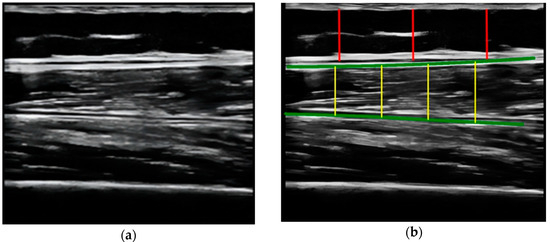

- Compare the measurements of the unilateral (right) RF of the patients performed by the expert evaluator (rater 1) using the standard tools included in the ultrasound image device (i.e., method A), see Figure 2, with those obtained by applying the PIIXMEDTM Ultrasound Imaging System (Dawako Medtech S.L., Valencia, Spain) (rater 2) (i.e., method B) [15,16,17,18,19] on the same acquired raw images, see Figure 3 and Figure 4.

Figure 4. (a) Acquired raw ultrasound image of the unilateral (right) quadriceps rectus femoris muscle in the longitudinal plane obtained by rater 1 and scaled by PIIXMEDTM (rater 2—method B); (b) PIIXMEDTM processing (i.e., rater 2—method B) of the automatically segmented longitudinal ultrasound image, upper and deep aponeurosis (green color), to obtain the results of the SFT (three red lines and their mean value) parameter and the longitudinal thickness (four yellow lines and their mean value), MT, not used in this study. - Calculate and evaluate the inter-rater reliability of quantitative muscle architecture parameters (MAP) of the unilateral (right) RF measurements performed by the expert evaluator (rater 1) (i.e., method A) against the measurements using the automated PIIXMEDTM Ultrasound Imaging System (rater 2) (Dawako Medtech S.L., Valencia, Spain) (i.e., method B) on the same acquired raw images.

The MAP variables measured and analyzed by PIIXMEDTM in this study were the RF thickness and cross-sectional area in the transverse plane (MT, and CSA) and the subcutaneous fat thickness (SFT) in its longitudinal plane.